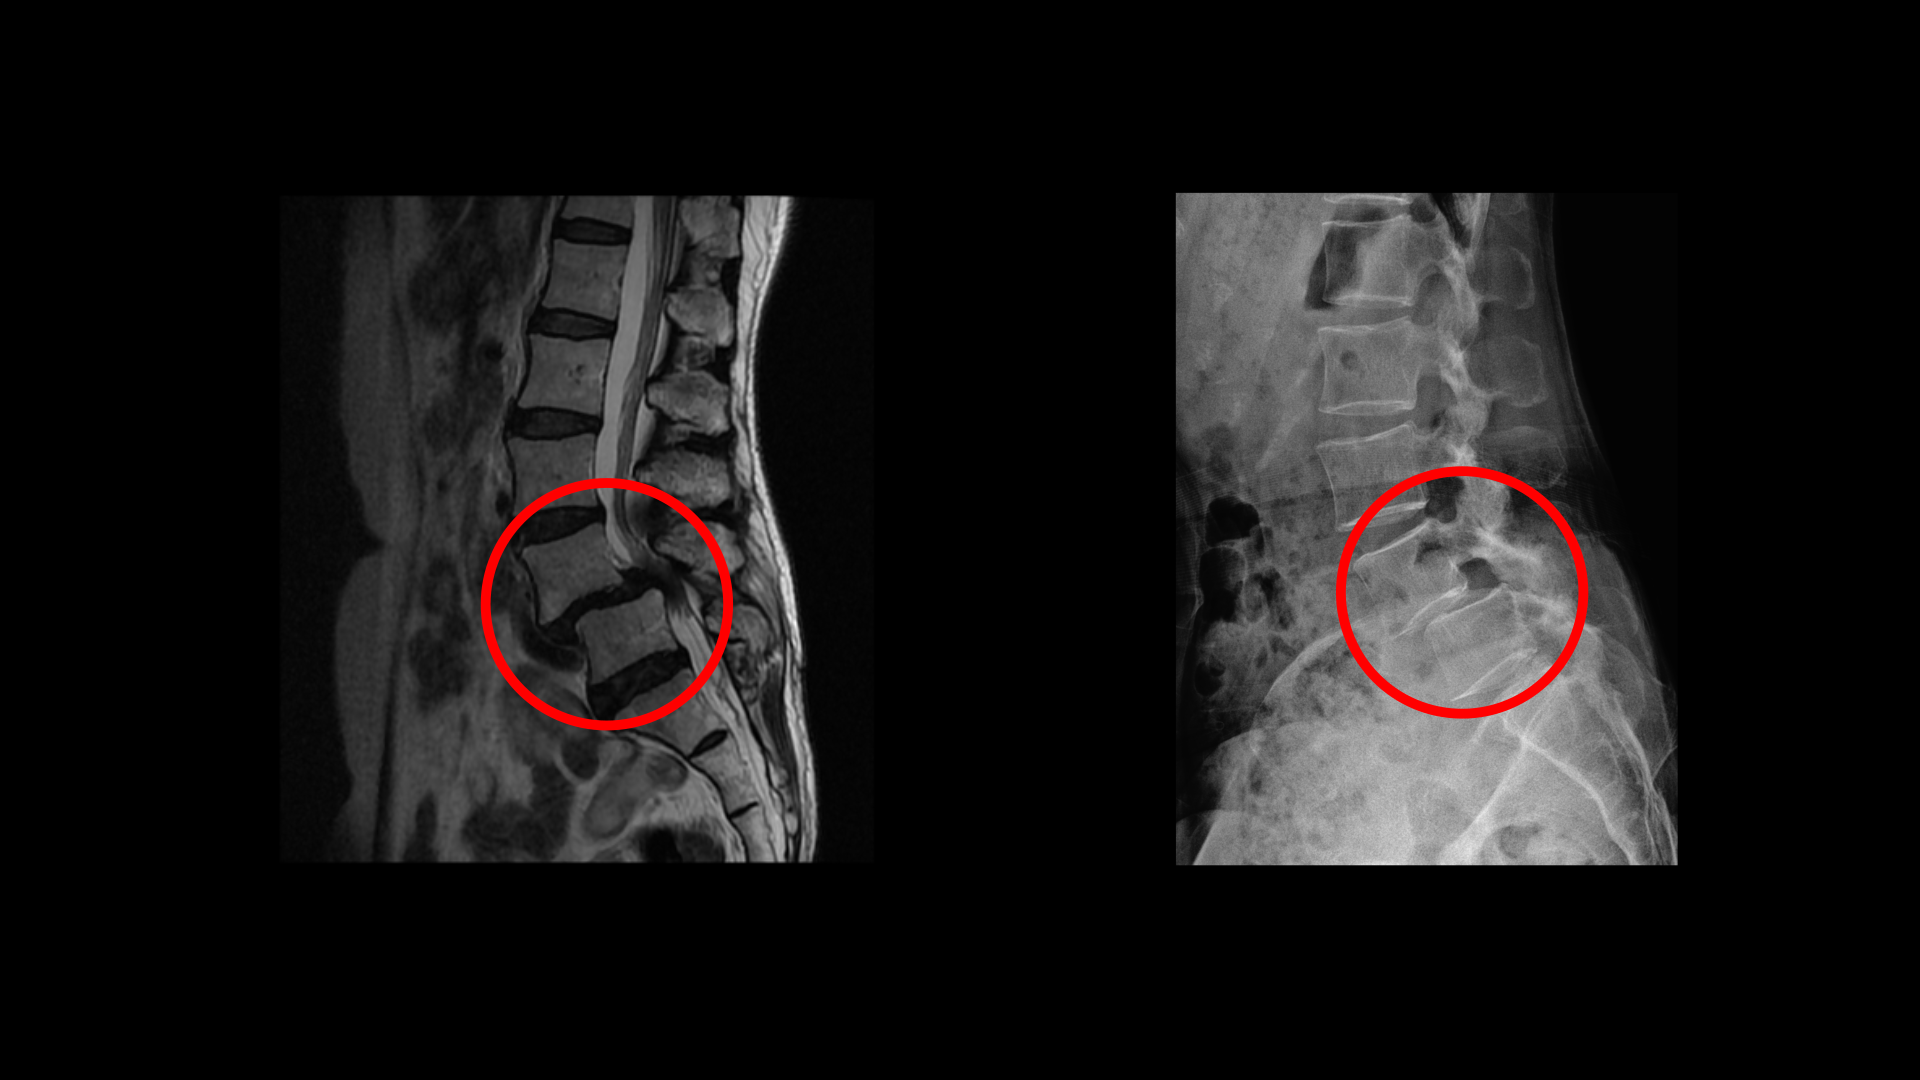

이 환자분 상태를 먼저 설명 드린 후 이분 말씀을 들어보겠습니다. 이분 MRI를 보면 전방전위증과 척추관협착증이 정말 심합니다.

위 뼈가 거의 절반 가까이 밀려 나가있고 두 마디의 척추관이 정말 심하게 막혀서 보시다시피 신경이 제대로 보이지 않습니다.